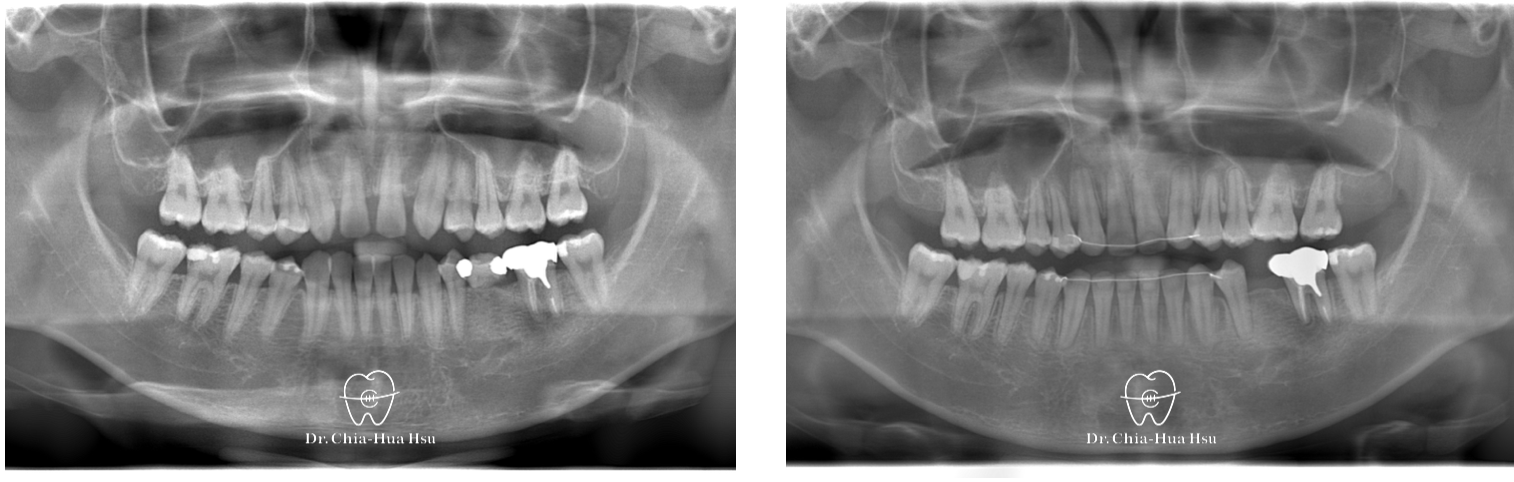

治療前

• 問題分析:患者除了門牙牙縫、齒列不正問題,有先天性缺失上顎雙側側門牙兩顆以及左下第二小臼齒,並且左下方有滯留的乳臼齒,治療難度高。

• 治療方式:使用傳統金屬矯正器,並搭配拉口內橡皮筋的方式來讓上顎後排牙齒往前移動,以關閉缺牙縫隙。

• 治療結果:改善缺牙、縫隙,以及上下顎咬合關係,左下乳臼齒拔除後以一顆植牙重建。